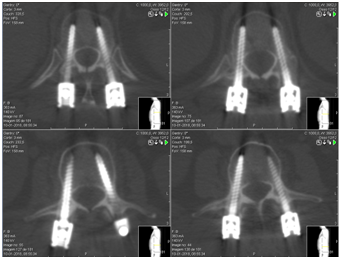

Wang considered PF as a good therapeutic option in type A thoracolumbar fractures, with significant differences between this technique and traditional open surgery, regarding incision size (Figure 1) blood loss, surgical time, hospitalization period, need for blood transfusion and postoperative analgesia. However, there were no differences between these two techniques regarding the radiological results obtained (Figure 2-6).13

Figure 2-5 Postoperative computerized axial tomography images after percutaneous fixation